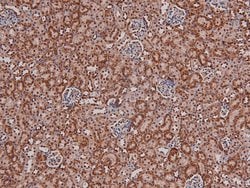

Phospho-p27 Kip1 (Thr157) Polyclonal Antibody for Western Blot, ICC/IF, IHC (P)

| Immunohistochemistry (Paraffin), Western Blot, Immunocytochemistry | |

| A synthesized peptide derived from human CDKN1B(Accession P46527), corresponding to amino acid residues around phosphorylated Thr157. | |